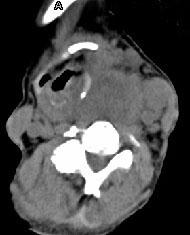

问题 女,64岁,发现双甲状腺肿大一月余,CT如图所示,最可能诊断为 ( )

选项 A、甲状腺转移瘤 B、甲状腺结核 C、甲状腺腺瘤 D、甲状腺癌并淋巴结转移 E、结节性甲状腺肿

答案 D